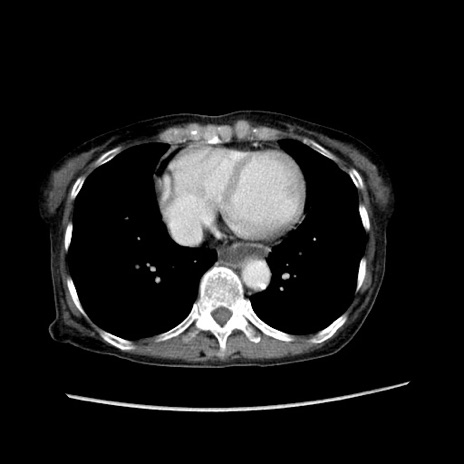

症例25(横断像)

【症例】80歳代女性

【主訴】胸のつかえ感

【現病歴】約9時間前に食後から胸のつかえた感じあり、嘔吐あり、来院。

【既往歴】胃癌(全摘)、胆摘、虫垂炎

【身体所見】心窩部に圧痛あり、反跳痛なし。

【データ】WBC 5700、CRP 0.05